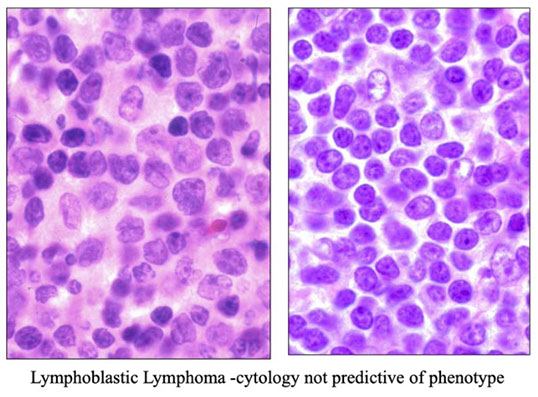

Lymphoblastic lymphoma, the cytology not predictive of phenoty[e (left is B-cell, right is T-cell, or maybe vice versa? you would never know)